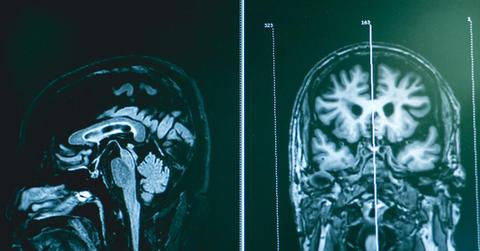

A neurologist or health care provider usually diagnoses frontotemporal dementia. You may undergo a physical and neurological examination, which includes lab tests and imaging tests to review the areas of the brain that are possibly deteriorating. Tests can include:

- Magnetic resonance imaging (MRI) scans.